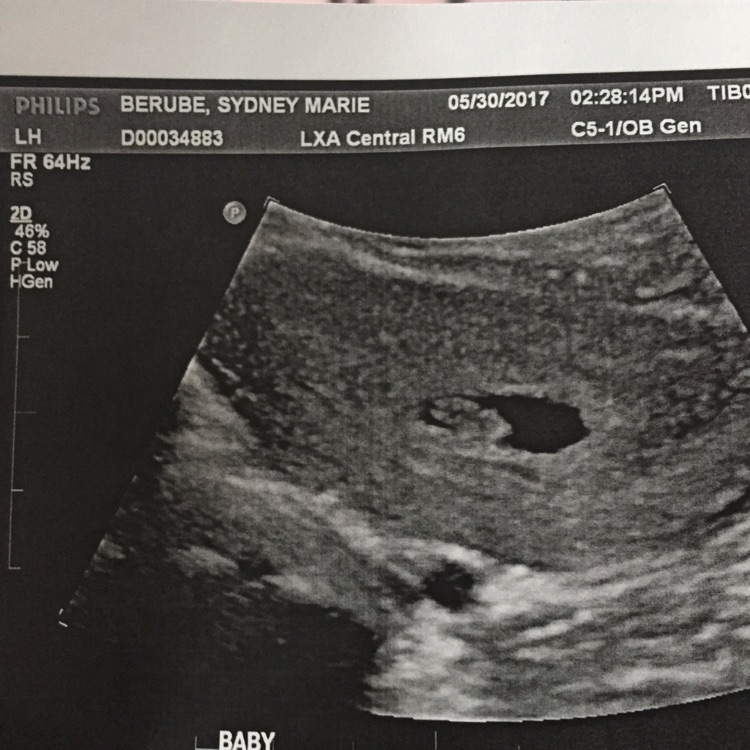

Just had my first ultrasound baby#2 due date is now January 13,2018. I'm very nervous now, I wonder how my daughter going to take it once baby gets here? she's only 8 months old now. I'm very excited but nervous at the same time. Anyone else feel me?